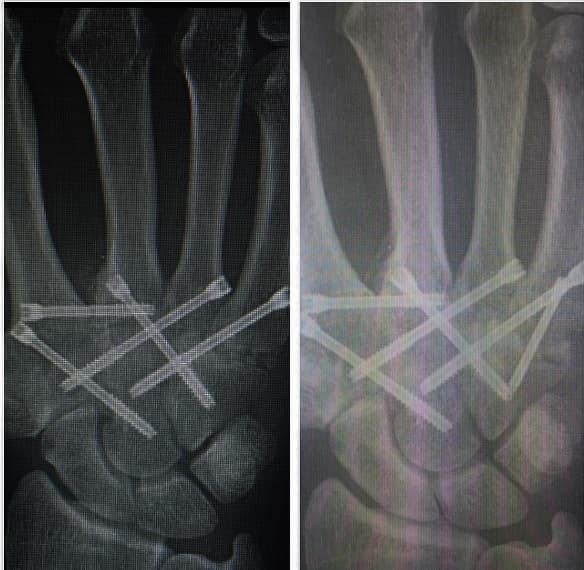

Imagen Instagram Khan

El británico tenía problemas desde hace 10 años, el excampeón escribió en su cuenta de Instagram que espero tanto tiempo porque quería quedar bien y no arriesgarse, dijo que la tecnología ha avanzado y por eso decidió someterse a la operación en este momento.

Khan comentó que le quitaron un pedazo de hueso de la cadera para insertarlo en el dedo, afortunadamente para el boxeador todo fue un éxito, el doctor le dijo que podrá empezar a golpear en cuatro semanas.